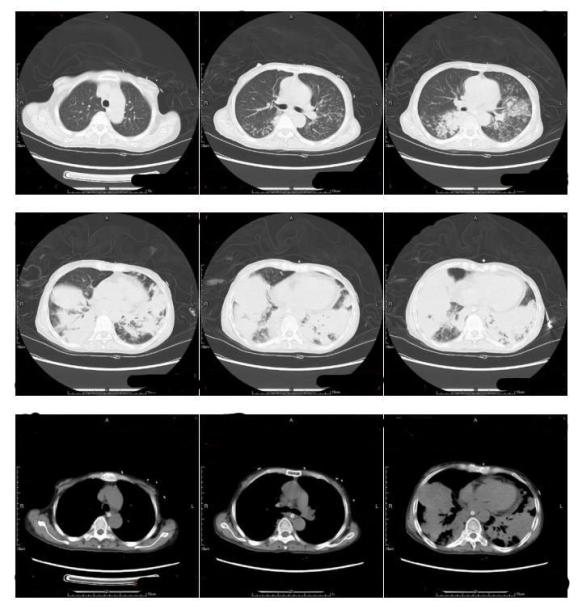

2022年9月14日至我院就诊,查胸部CT(图1):两肺炎症伴实变,两肺多发小结节,拟炎性病变;两侧胸腔积液。纵膈淋巴结增大。心脏增大,心包积液,贫血改变。血气分析(吸氧10L/min):pH 7.51,氧分压 8.68kpa,二氧化碳分压 5.44kpa,标准碳酸氢根 31.1mmol/L、标准剩余碱 7.9mmol/L。

图1 胸部CT(2022.9.14)血常规:WBC 18.89x109/L,N 94.7%,L 3.3%,RBC 2.91x1012/L,Hb 79g/L,PLT 353x109/L,CRP 102mg/L。现患者为求进一步诊治收入我科。

9月21日患者尿液浑浊,絮状物增多,尿培养回报白假丝酵母菌,予以加用大扶康抗真菌治疗;9月23日(图2)复查胸部CT部分较前好转,氧合有好转,吸氧浓度下降至50%左右,低热有反复,咳嗽、咳痰不明显。

图2 胸部CT(2022.9.23)9月25日因痰培养为耐药鲍曼不动杆菌,根据药敏改哌拉西林他唑巴坦为头孢哌酮舒巴坦、米诺环素、多黏菌素抗感染,9月30日因CMV DNA定量>103IU/mL,加用更昔洛韦抗病毒;10月7日因再次发热,痰涂片找到阳性球菌,加用万古霉素抗感染及对症支持治疗。

后患者症状好转,10月8日(图3)复查CT较入院时实变明显有吸收好转,仍有两肺渗出,考虑实变基础上继发感染,但患者无发热,呼吸道症状不明显,鼻导管吸氧,吸氧3L/min呼吸平稳,血象稳定,PCT正常,转至康复医院继续治疗。

图3 胸部CT(2022.10.8)讨论